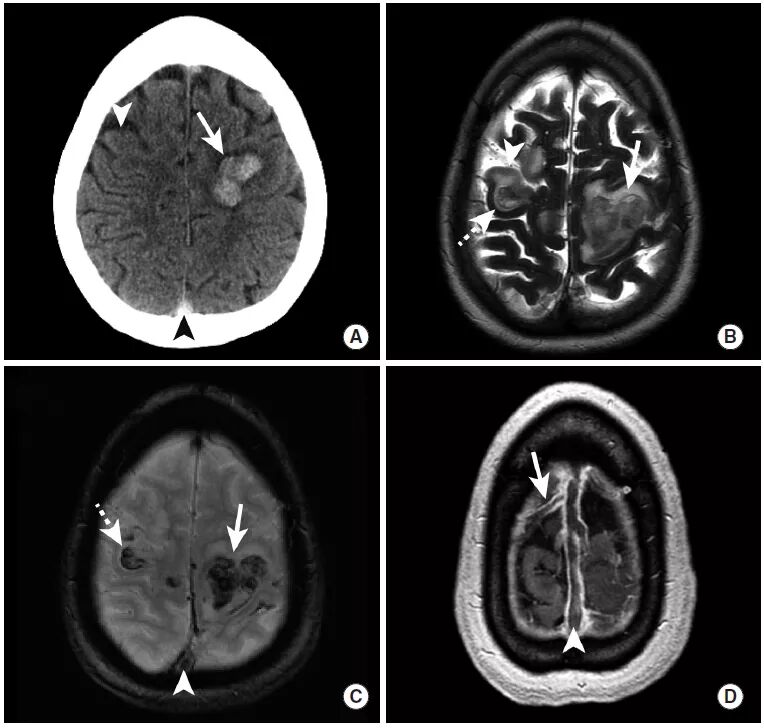

图1

本例为车祸导致的外伤性蛛网膜下腔出血。

图A:平扫CT显示脑沟内高密度影(长尾箭头),此外还可以看到左侧的硬膜下血肿(三角箭头)以及右顶骨处的帽状腱膜下血肿(虚线箭头)。

图B:MRI FLAIR序列同样可见脑沟内高信号,证实了蛛网膜下腔出血的存在,同时可见左侧硬膜下血肿和右侧帽状腱膜下血肿。

图C:GRE序列上,蛛网膜下腔出血和硬膜下血肿表现为低信号。